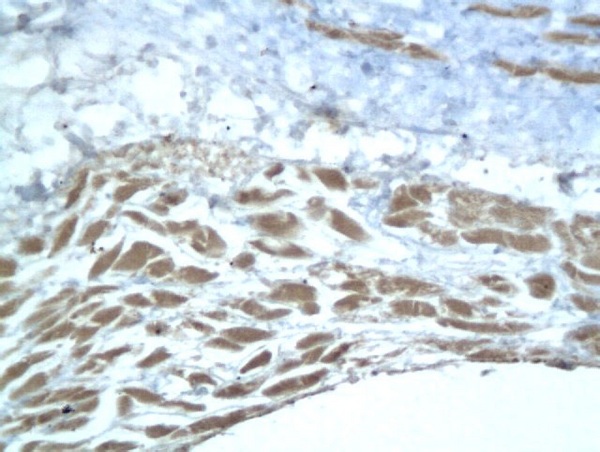

ACAN Polyclonal Antibody

• IHC-P

Product Name ACAN Polyclonal Antibody

Applications WB, ELISA, IHC-P, IHC-F, IF(IHC-P), IF(IHC-F), IF(ICC)

Background This proteoglycan is a major component of extracellular matrix of cartilagenous tissues. A major function of this protein is to resist compression in cartilage. It binds avidly to hyaluronic acid via an N-terminal globular region.

IHC-P 1:200-400